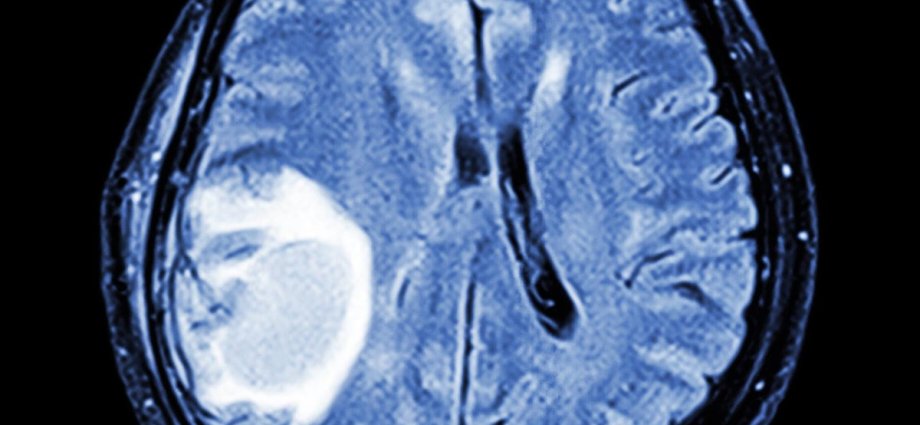

One study showed that a subset of cells in human brain tumours are similar to embryonic progenitor cells – a kind of cell in the embryo that can change into specific types within a particular brain region – raising the possibility that such tumors may hijack developmental processes to drive malignancy.